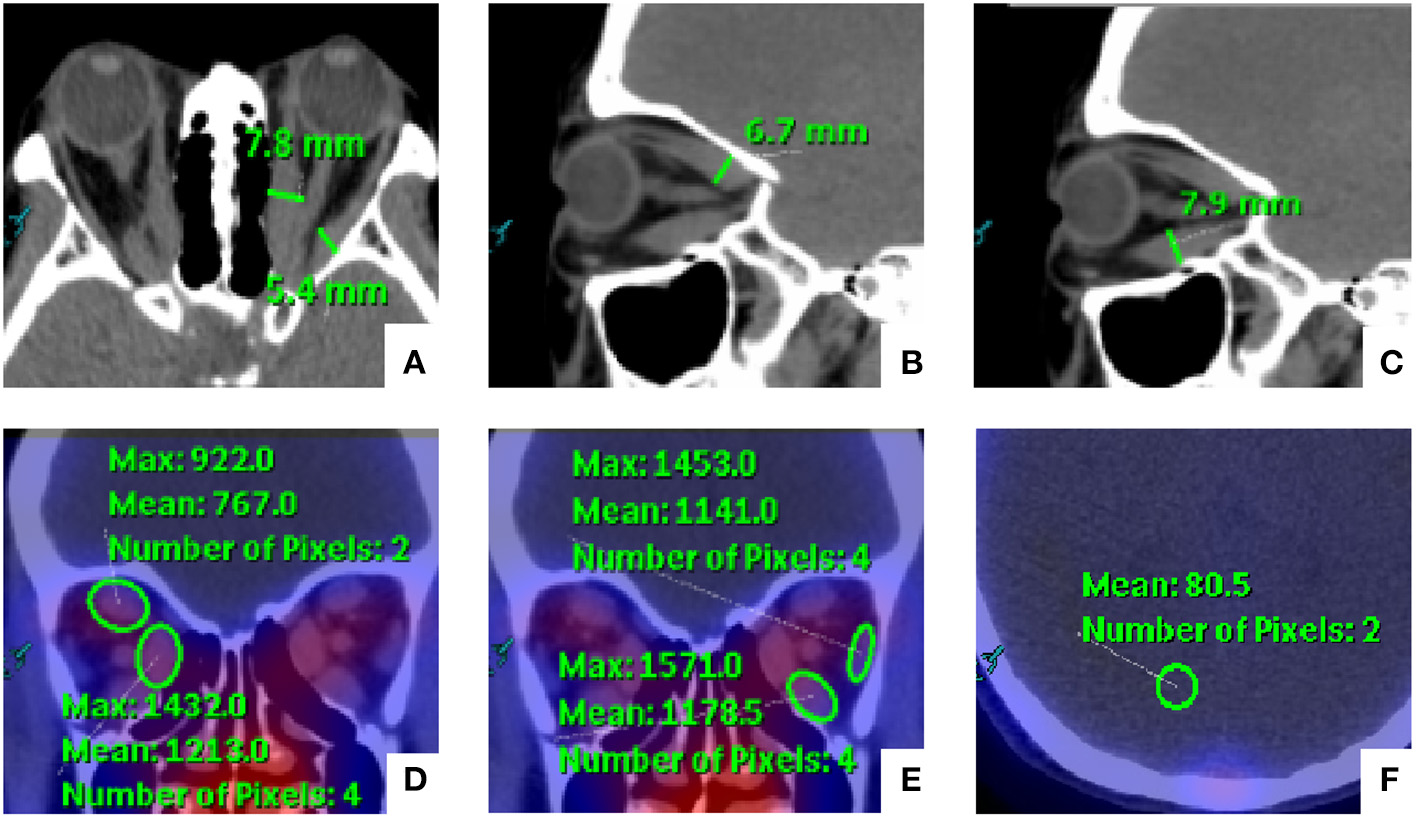

Manual rigid registration of SPECT and CT images was carried out on the EBW workstation. Two experienced nuclear medicine specialists (MZ and CZJ) who were blinded to the SPECT/CT results evaluated the orbital SPECT/CT images together. The thickness and DTPA uptake of EOMs were evaluated by the two readers. Horizontal diameters of the medial rectus (MR) and lateral rectus (LR), and the vertical diameters of the superior rectus (SR) and inferior rectus (IR) were measured on the series of images. In addition, the DTPA uptake was determined by manually placing a round region of interest (ROI) with the consensus highest uptake of each EOM on the CT attenuation-corrected SPECT images. The background uptake value was similarly determined through analogous placement of an ROI on the occipital lobe based on our previous studies (12). The methods for SPECT/CT parameter measurement are illustrated in Figure 1. For the same patient, the value of uptake ratio (UR) was calculated as the ratio of the maximum EOM uptake value to the maximum background uptake value. Furthermore, we chose the highest value of thickness and UR among the four EOMs as the maximum thickness (Tmax) and the maximum UR (Umax).

Figure 1

Schematic diagram for the measurement of orbital single-photon emission computed tomography/computed tomography (SPECT/CT) semi-quantitative parameters of extraocular muscles (EOMs). (A–C) The medial rectus (MR) and lateral rectus (LR) were measured on the axial images, and the vertical diameters of the superior rectus (SR) and inferior rectus (IR) were measured on the sagittal images. In addition, (D,E) the EOM uptake values were determined by manually placing a round region of interest (ROI) within the consensus highest uptake portion of each EOM on the CT attenuation-corrected SPECT images. (F) The background uptake value was similarly determined through the analogous placement of an ROI on the occipital lobe.